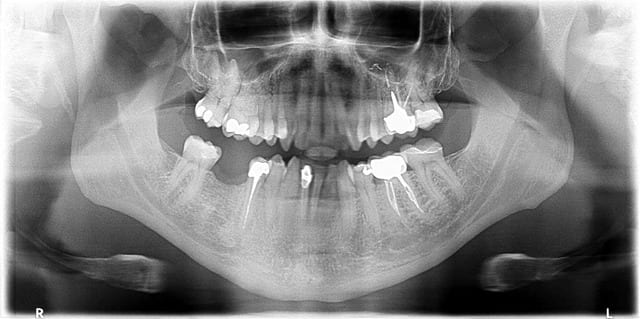

Pano avec le kodak 9000

Le patient est bien placé, il n'a pas bougé, et pourtant c'est inexploitable.

Si je peux me permettre fatboy ton patient n'a pas la langue au palais sur ton cliché, erreur très répandue qui est responsable du large dôme sombre qui s'étale entre le dos de la langue et le palais osseux. Demande au patient de 'sucer' la tige sur laquelle il mord (je te laisse libre de trouver la formule verbale qui convient et ne le fera ni rougir ni éclater de rire...), cela permet en général de lui faire plaquer la langue au palais correctement et la lecture de la région apicale est nettement améliorée.

Cela dit, dans mon cabinet précédent javais moi aussi une pano Kodak qui m'avait beaucoup déçue. Le cliché que tu présentes là étant quasiment le top de ce que j'arrivais à obtenir. Leurs capteurs RVG étaient par contre très bons.